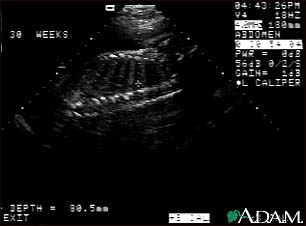

Ultrasound, normal fetus - spine and ribs

This is a normal fetal ultrasound performed at 30 weeks gestation. In the middle of the screen, a clear outline of the spine and ribs is visible. The cross hair is between two ribs just above the spine.